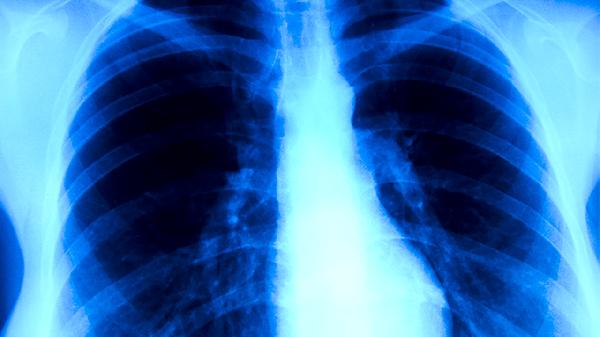

肺癌会咳什么颜色的痰 盘点肺癌的5个症状

肺癌患者可能咳出白色、黄色、绿色或带血丝的痰液,痰液颜色与病情进展或感染相关。肺癌的典型症状主要有咳嗽、痰中带血、胸痛、呼吸困难和体重下降。